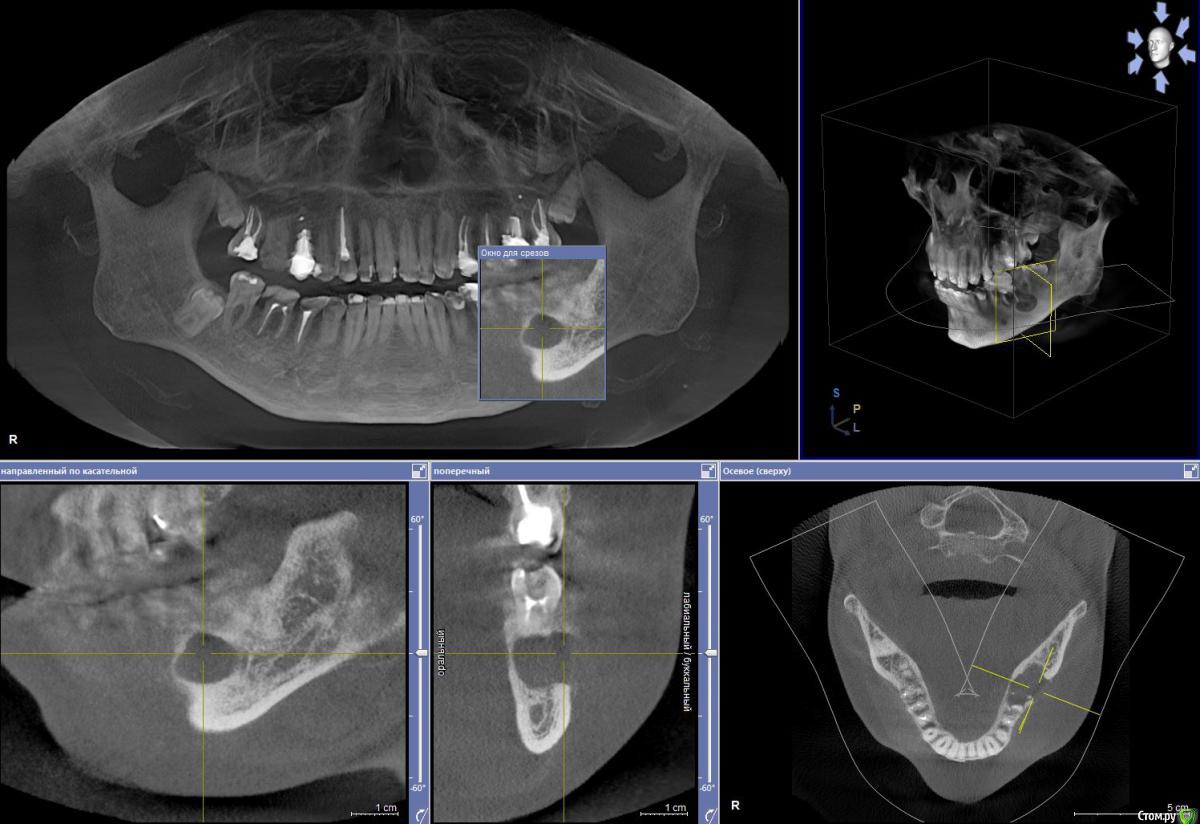

Anna275 Опубликовано 18 октября, 2018 Поделиться Опубликовано 18 октября, 2018 Здравствуйте! Несколько дней назад мужу диагностировали на КТ радикулярную кисту в нижней челюсти слева. Врач учреждения, где делали КТ, расписал следующий план лечения: удаление трех зубов (6-ка, 7-ка, 8-ка), цистоэктомия, костная пластика челюстно-лицевой области (замещение костного дефекта или заполнение биоактивным материалом), применение препарата PRF (2 пробирки). Ну и в дальнейшем установка имплантов. Мы пока пребываем в шоке, уже три дня читаю интернет, записались на пару консультаций в разные клиники, но пока время не подошло; параллельно решила попросить совета на этом сайте. Уважаемые стоматологи, вы согласны с тем, что требуется удаление аж трех зубов??? Консервативное лечение в нашем случае уже никак? Для информации - в 6-ке стоит штифт.Прошу прощение за техническую неподкованность, прикрепляю копии снимков, если нужно (и можно на этом сайте - могу выложить результаты КТ в формате iso). Заранее спасибо! Ссылка на комментарий

DmitrySH Опубликовано 18 октября, 2018 Поделиться Опубликовано 18 октября, 2018 Шестой - 100% удаление из за сильного разрушенияВосьмой - удаляется из-за своей не функциональности Седьмой - сам по себе не так плох, можно и попытаться сохранить, только это усложнит и растянет всю работу Удаление трех сразу и имплантация -более прогнозируемо Ссылка на комментарий

red_butler Опубликовано 19 октября, 2018 Поделиться Опубликовано 19 октября, 2018 Перелечить седьмой. Убрать шестой (без вариантов) на сколько получится вычистить оболочку кисты через лунку. Через пару тройку месяцев принимать решение о цистэктомии. Восьмой убрать до протезирования седьмого.P.s. на верхней челюсти два кандидата на удаление 1 Ссылка на комментарий

kriokov Опубликовано 19 октября, 2018 Поделиться Опубликовано 19 октября, 2018 1 этап удалил бы три зуба , 6, 7, 8, с одномоментной цистэктомией (удаление кисты) через лунки удаленных зубов, никакие бы костные заменители для восстановления дефекта на первом этапе не применял.(дефект маленький , наружная кортикальная везде почти целая, заживет сам)2. через 6 месяцев повторно клкт этой зоны, с целью решения вопроса о возможности установки имплантатов и необходимости "костной пластики" 1 Ссылка на комментарий

red_butler Опубликовано 19 октября, 2018 Поделиться Опубликовано 19 октября, 2018 А это какие именно? (для информации)1.5 2.6 и возможно 2.4 1 Ссылка на комментарий

Bier Опубликовано 20 октября, 2018 Поделиться Опубликовано 20 октября, 2018 Если хочется максимально спасать зубы, то 7й можно перелечить. 6й однозначно удаляется.в 8м смысла нет. Ссылка на комментарий